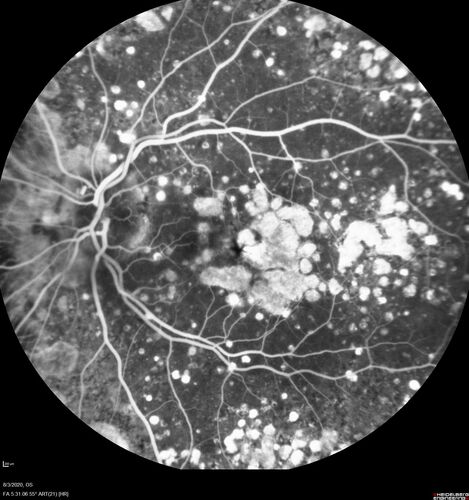

Dry AMD geographic atrophy and cystoid macular edema

79 year old vision is in for a checkup with no visual complaints in the left eye.  This is her better eye.  VA 20/200 OD, 20/50 OS.  3 years ago she had a CRVO in the left eye.  She is also diabetic for 20 years, has carotid insufficiency and anemia.  Left eye shows CME.  This was not treated and the vision improved to 20/40 over the next year although mild edema persisted.